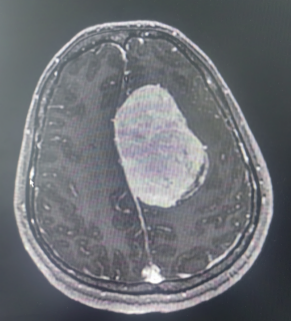

患者系中年女性,因出现偏侧肢体活动不灵和头痛症状,经检查发现颅内大脑镰旁长有一直径7cm的巨大肿瘤。肿瘤位于大脑的运动功能区,血供丰富,这一区域的手术风险极大。在决定手术治疗之前,神经外科医生与患者家属进行了充分的沟通,详细解释了手术的必要性、可能的风险和并发症,包括出血、感染、血管和神经损伤以及脑功能障碍等。家属在充分了解情况后,同意进行手术。面对这一复杂病例,我院迅速组织了由神经外科、麻醉科、心内科、输血科等多个科室的专家团队进行会诊,共同制定了先介入栓塞,再手术切除的治疗方案。

神经外科血管介入组曲友直副教授、崔刚副教授和高攀主治医师对肿瘤进行了瘤栓塞治疗,有效减少了肿瘤的血供,为后续的手术切除降低了风险。栓塞治疗后,神经外科王睿智副主任、高李贵副教授和董全主治医师在麻醉科、心内科、输血科等科室的全力配合下,凭借精湛的医术和丰富的临床经验,成功为患者切除了病变。手术过程中,麻醉科吕建瑞主任团队全程监控患者的生命体征,确保麻醉安全;心内科团队随时准备应对可能出现的心脏问题;输血科团队则确保充足的血液供应,以备不时之需。多学科的通力合作,为手术的成功提供了坚实的保障。